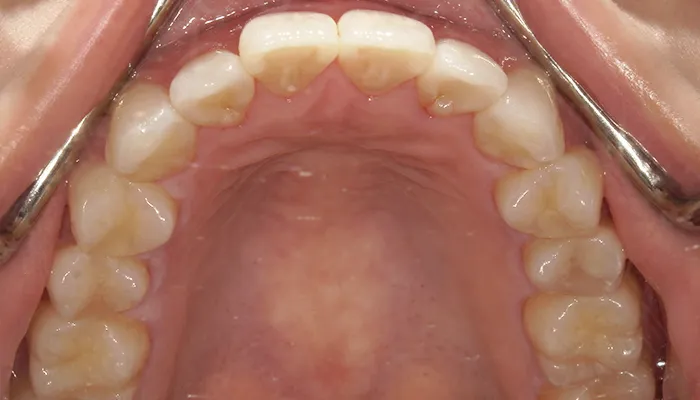

治療後

治療終了後の完成した口腔内と

レントゲン写真

右下5番のインプラントは良好に骨結合し、自然な形態と色調の補綴物を装着しました。

インビザライン矯正により歯列が整い、清掃性・咬合バランスともに改善しました。

ホワイトニングにより歯全体の色調が明るくなり、笑顔の印象が大きく改善しました。

患者様は審美性・機能性ともに大変満足していらっしゃいました。